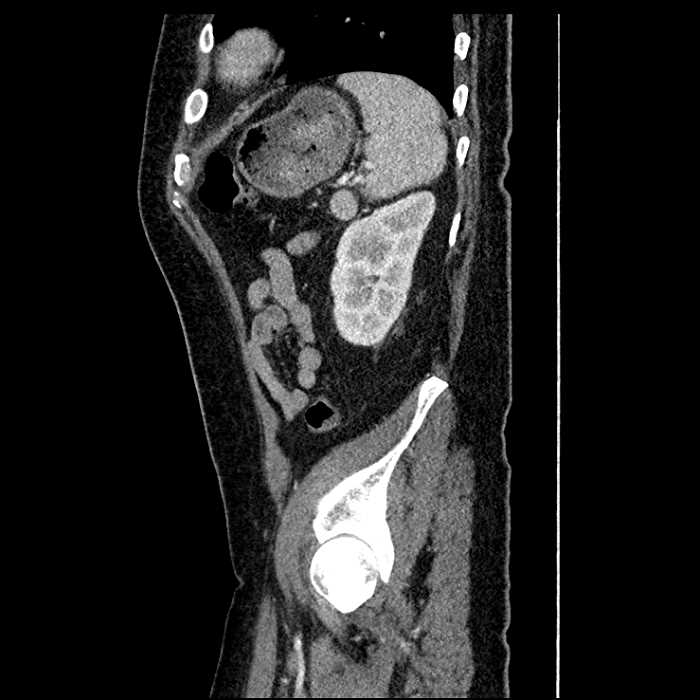

Age: 63

Sex: Male

Indication: Abdominal pain

• Large fluid density structure in hepatic segments 7 and 8 measuring 10 x 7 x 7 cm with internal septation and circumferential ill-defined low density compatible with edema

• Clearly marginated fluid density structure in segment 7 and several other scattered tiny hypodensities, which likely represent cysts

Acute sigmoid diverticulitis complicated by a small contained perforation and a large abscess in the right hepatic lobe. Additional small subcapsular abscesses along the anterior margin of the left hepatic lobe.

Additionally, loss of the normal fat plane between the peridiverticular collection and adjacent thickened loops of small bowel raises the potential for an enterocolonic fistula.

• The classic CT imaging appearance is a double target sign with internal low density surrounded by an internal enhancing rim (capsule) and a low density external rim (edema)

Hepatic abscess showing the double target sign with low density internally surrounded by a thin inner enhancing rim (red arrow) and ill-defined outer low density rim (yellow arrow). Blue arrow indicates an internal septation. Red arrows: additional smaller subcapsular abscesses. Red arrow: focal contained perforation associated with diverticulitis.